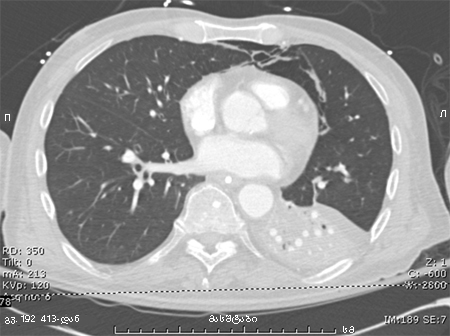

პაციენტის კომპიუტერული ტომოგრაფია, რომელსაც აქვს დიდი, მკვრივი ინფილტრაცია მარცხენა ქვედა წილში.